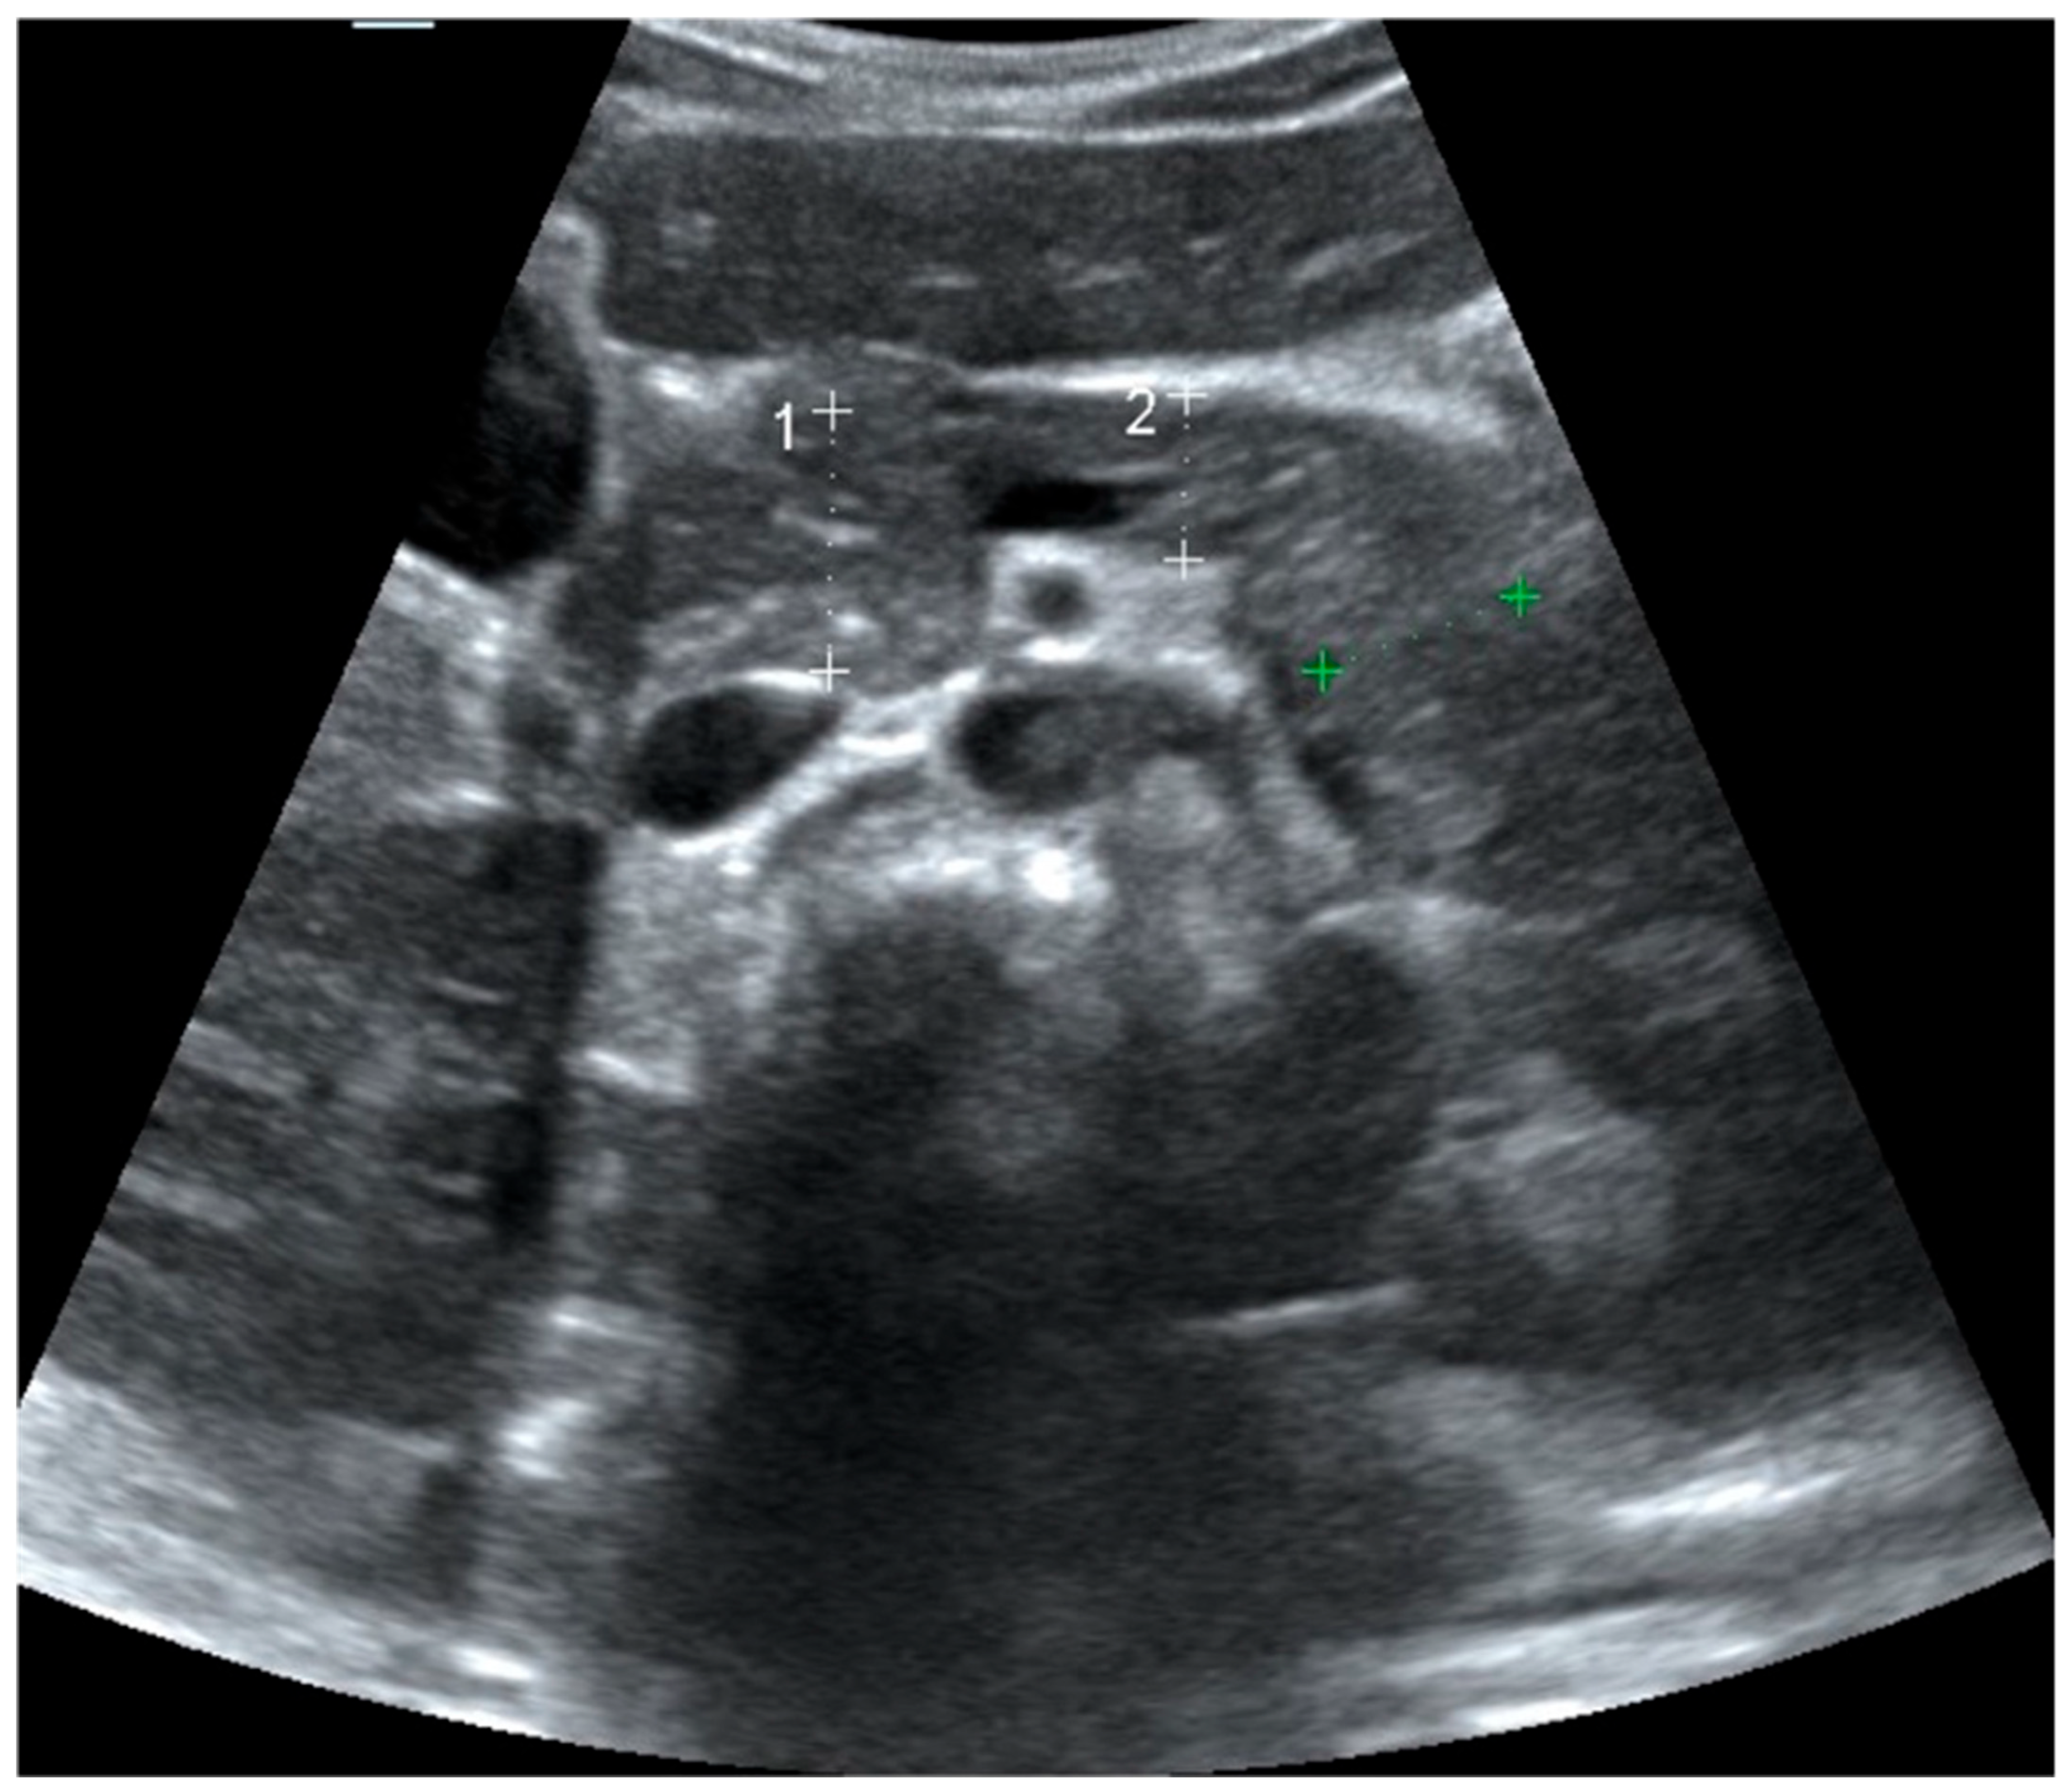

An isoechoic pancreas is defined as having an echo intensity equal to or slightly higher than that of the liver. Echogenicity was assessed by comparing the pancreas to the adjacent liver at similar imaging depths and categorized as isoechogenic or non-isoechogenic (hypoechogenic or hyperechogenic). This comparative assessment between the pancreas and liver is a standard approach in radiological imaging [9,10]. Pancreatic images from participants illustrating echogenicity patterns—isoechogenic (panel a) versus non-isoechogenic (panel b)—are presented in Figure 2. Alterations in echogenicity, such as areas of hypo- or hyperechogenicity, may indicate pathological conditions such as acute or chronic pancreatitis [11]. To enhance pancreatic visualization, patients fasted for at least six hours to reduce intestinal gas and peristaltic motion. Additionally, 200 mL of water was administered before the examination to improve pancreatic delineation during scanning [12].

Figure 2. Ultrasound image showing pancreas echogenity compared to liver. (a): Ultrasound image showing pancreas (arrow) with equal echogenity compared to liver (arrowhead). (b): Ultrasound image showing hyperechoic pancreas (arrow) compared to liver (arrowhead).